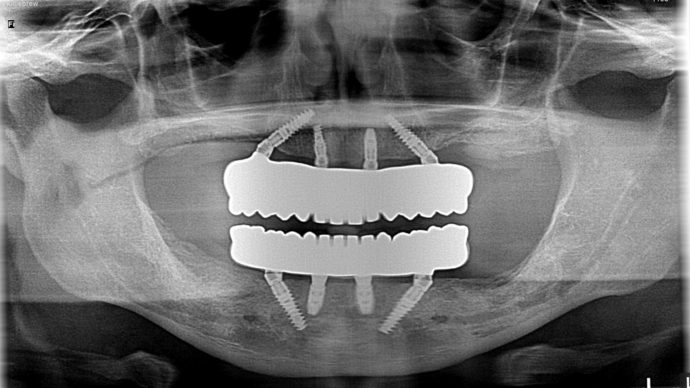

This busy business executive from NY suffered from chronic gum disease (periodontitis) due to genetics and unknown factors and had been to multiple dentists over the years and was tired of getting deep cleanings and still end up with several loose teeth in the mouth with massive bony destruction. As a young busy professional, he researched on getting the most scientific and durable treatment which could be done without several years in treatment and found Dr Bidra online. Dr. Bidra was able to successfully accomplish all his treatment goals by extracting all his teeth and installing Upper and Lower All on 4 implant bridges in 1 day. Most importantly, Dr Bidra did not need to perform any bone grafting procedures to accomplish this treatment.

Procedures : extractions, new implants, All on 4 , All on X, Teeth in a day, no bone grafting and full mouth reconstruction with monolithic zirconia bridges.